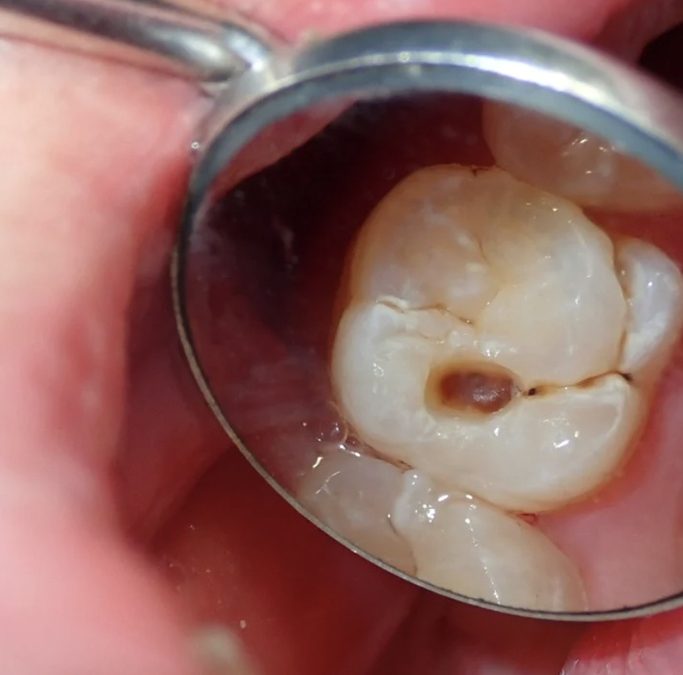

Les caries se forment lorsque les bactéries présentes dans la plaque dentaire transforment les sucres des aliments en acides, qui attaquent l’émail des dents.

Les adultes sont particulièrement exposés aux caries sur les surfaces dentaires plus difficiles à atteindre, les dents déjà restaurées ou les racines exposées suite à une récession gingivale.